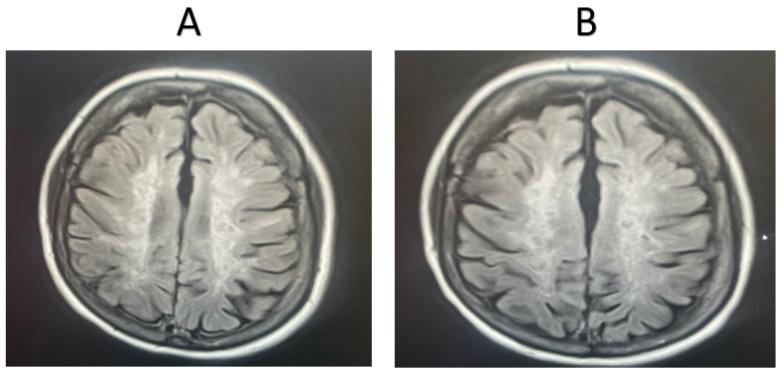

This study included 40 healthy individuals as a control group and 75 MS patients, divided into two groups: 45 MS patients receiving fingolimod treatment (MSW) and 30 patients taking other medications (MSOs). Blood samples (3 mL) were collected from all participants, and the mRNA relative expression of cytokine genes (, , , and ) was measured. Additionally, MRI images of MS patients undergoing fingolimod or other treatments were analyzed.

The MSO patient group displayed higher mRNA expressions of , , , and compared to the control group. Furthermore, , , and expressions were elevated in the MSO group compared to the MSW group. MRI scans showed significant improvement in MS patients taking fingolimod compared to those receiving other medications.

本研究纳入40名健康个体作为对照组,75名MS患者分为两组:45名接受芬戈莫德治疗的MS患者(MSW组)和30名服用其他药物的患者(MSO组)。采集所有参与者的血样(3毫升),检测细胞因子基因(、、、)的mRNA相对表达量。此外,对接受芬戈莫德或其他治疗的MS患者的MRI图像进行分析。

与对照组相比,MSO患者组的、、、的mRNA表达更高。此外,与MSW组相比,MSO组的、和表达升高。MRI扫描显示,与接受其他药物治疗的患者相比,服用芬戈莫德的MS患者有显著改善。